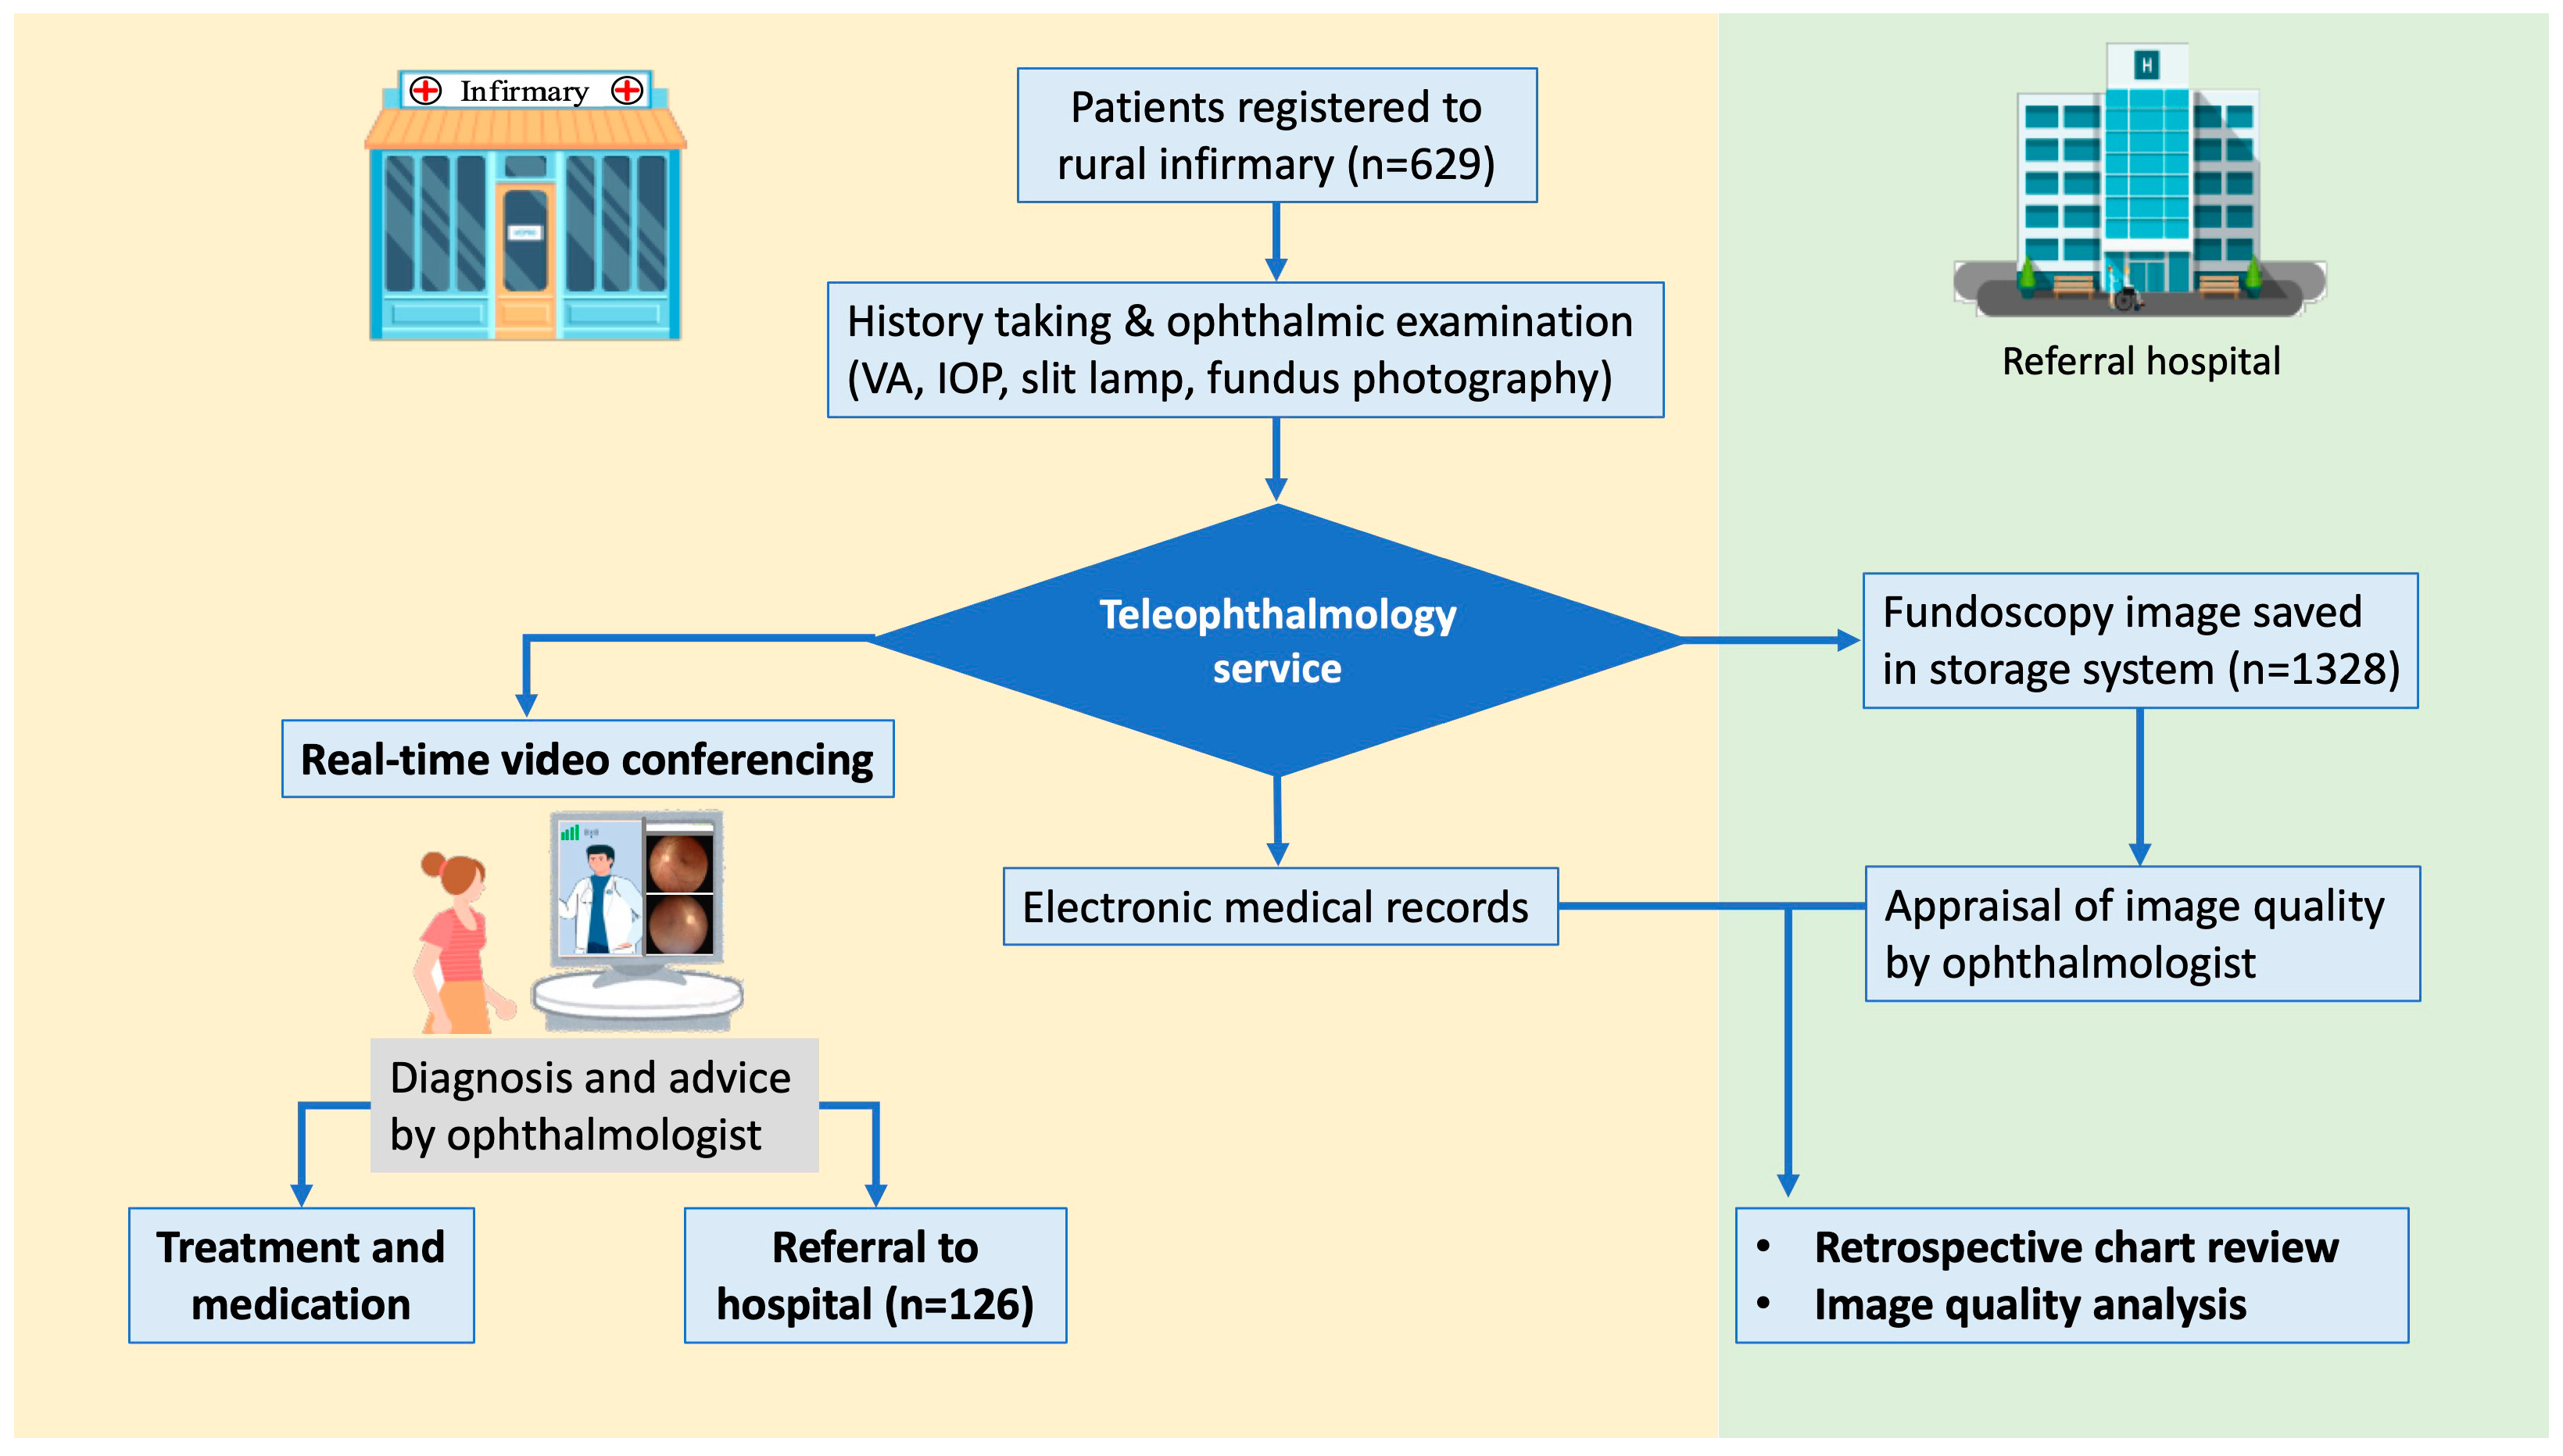

2. Materials and Methods

2.1. Participants and the Setting

2.2. Ophthalmic Examination, Image Acquisition, and Data Transmission

2.3. Clinical Diagnosis and Referral

2.4. Assessment of Diagnostic Agreement and Evaluation of Fundus Photographs